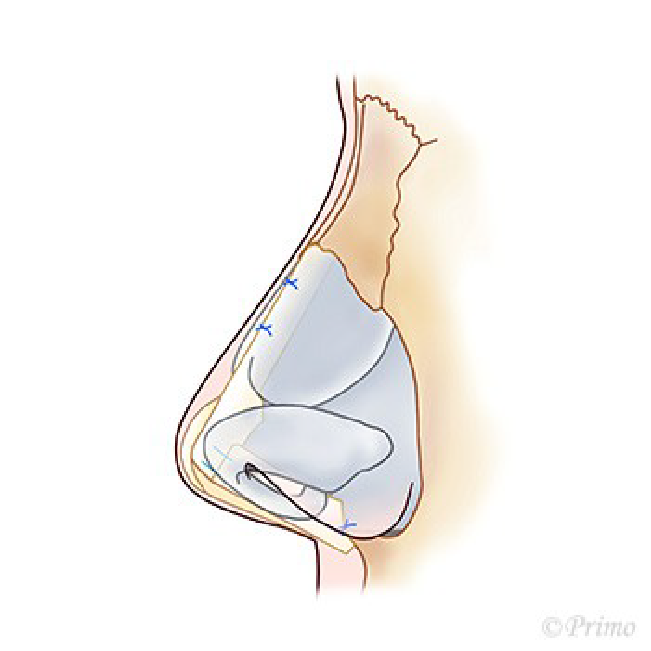

アプローチは経鼻柱切開(オープンアプローチ)から、術野を広く展開し、確実に操作を行います。鼻中隔軟骨に移植軟骨を組み合わせ延長し鼻の向き、高さを変えていきます。ご希望に応じ鼻の脂肪を部分的に除去し細っそりとさせたり、インプラントによる隆鼻術を併用し、より印象的な鼻に変化させます。鼻柱の傷あとはあまり目立ちません。

青い部分が移植した軟骨です。この軟骨の固定により、鼻の高さ、細さ、向きが大きく調節できます。